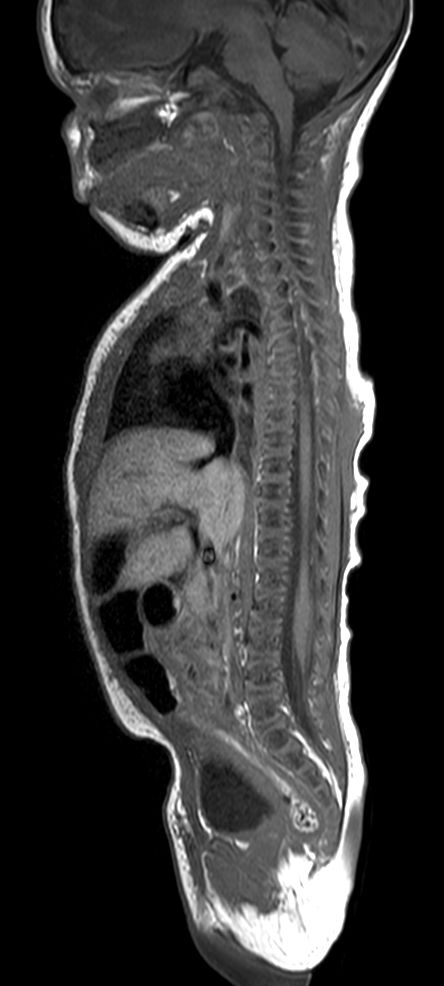

Pediatric Total Spine with spina bifida

Neonatal patient, 5 days old, with spina bifida